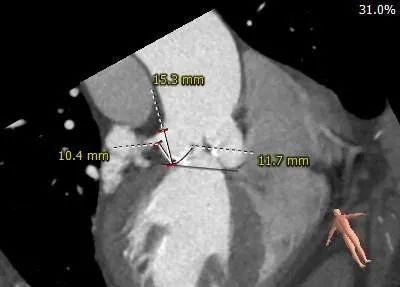

主动脉根部测量:

推荐20mm球囊预扩,球扩时关注冠脉灌注情况,预装AV23瓣膜,建议瓣环下零位左右定位释放。